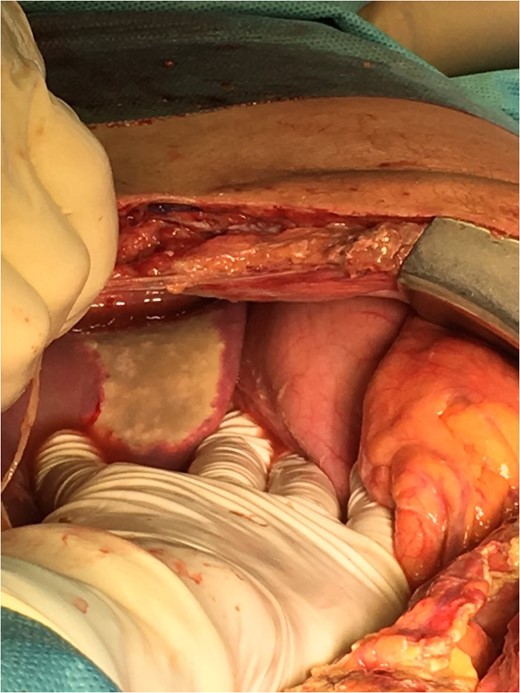

On the third laparotomy, three new necrotic lesions, two on the small intestine and one on the cecum, were found and suture repaired (Fig. 3). A necrotic lesion on the left lobe of the liver was also found (Fig. 4). On the fourth laparotomy, segmental enterectomy with anastomosis and cholecystectomy were performed due to anastomotic leak and a gangrenous gallbladder.